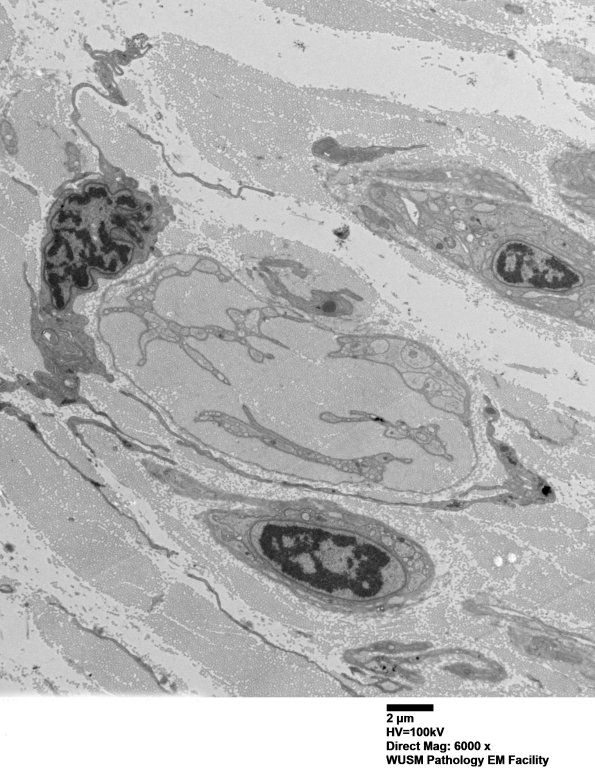

Washington University Experience | PERIPHERAL NEUROPATHY | 4 AXONAL DEGENERATION | 3 Electron Microscopy | 7A4A Chronic Degeneration (Case 33) Sural_048 - Copy

7A4A,B Another large collection of collagen and cells. Is the cell at the left margin a fibroblast or histiocyte? The cell at the lower margin in image 7A4B appears confidently to be Schwannian in origin. (electron micrographs)